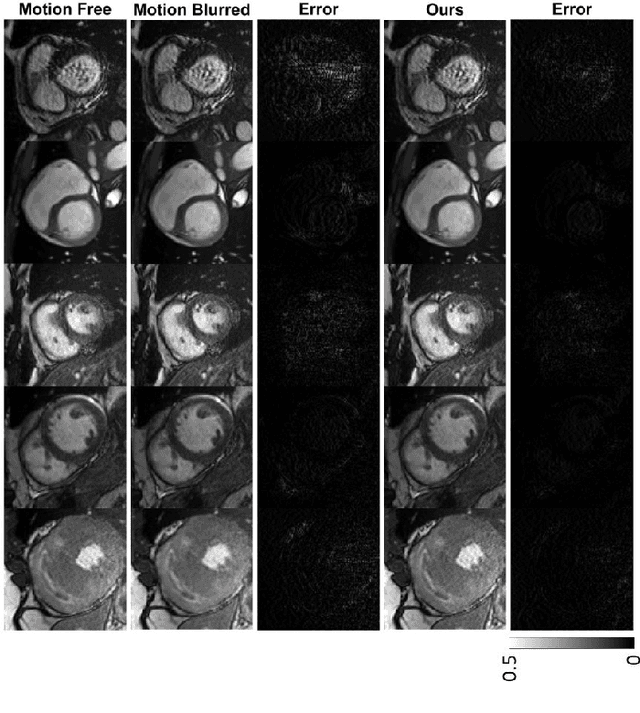

Cine cardiac magnetic resonance imaging (MRI) is widely used for diagnosis of cardiac diseases thanks to its ability to present cardiovascular features in excellent contrast. As compared to computed tomography (CT), MRI, however, requires a long scan time, which inevitably induces motion artifacts and causes patients' discomfort. Thus, there has been a strong clinical motivation to develop techniques to reduce both the scan time and motion artifacts. Given its successful applications in other medical imaging tasks such as MRI super-resolution and CT metal artifact reduction, deep learning is a promising approach for cardiac MRI motion artifact reduction. In this paper, we propose a recurrent neural network to simultaneously extract both spatial and temporal features from under-sampled, motion-blurred cine cardiac images for improved image quality. The experimental results demonstrate substantially improved image quality on two clinical test datasets. Also, our method enables data-driven frame interpolation at an enhanced temporal resolution. Compared with existing methods, our deep learning approach gives a superior performance in terms of structural similarity (SSIM) and peak signal-to-noise ratio (PSNR).